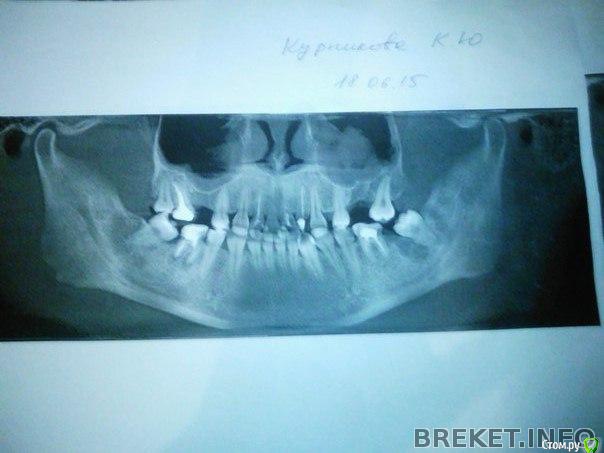

Force Опубликовано 10 апреля, 2016 Поделиться Опубликовано 10 апреля, 2016 Мда. 1. Что с центром на верхней челюсти? У вас смещение и я так понимаю, что для отсуствующей четверки промежуток с выравниванием центральной линии никто делать не планирует? 2. По профилю показания к ортогнатии (или выдвижению нижней челюсти вперед без хирургии) есть, но нужна более полная картина по плану лечения - какие зубы планируется имплантировать? и вообще какой план лечения полный 1 Ссылка на комментарий

Кристина93 Опубликовано 11 апреля, 2016 Автор Поделиться Опубликовано 11 апреля, 2016 (изменено) Центр будут выравнивать . но он меня мало волнует , так как почти не улыбаюсь . Имплантаты орт сказала устанавливать только после снятия брекетов , во время лечения она будет использовать микроимпланты ... Вы сказали что показания есть без операции , или я не так поняла... ?)( Изменено 11 апреля, 2016 пользователем Кристина93 Ссылка на комментарий

Кристина93 Опубликовано 24 апреля, 2016 Автор Поделиться Опубликовано 24 апреля, 2016 (изменено) Я имела ввиду костную гениопластику...как мне объяснили, берется фрагмент нижней челюсти и выдвигается вперед. Наверное, рано еще для опоры в боковом отделе...прошло полгода... В моем случае орт сказала что протезироваться только после снятия брекетов. Во время лечения будет использовать микроимпланты.... Изменено 24 апреля, 2016 пользователем Кристина93 Ссылка на комментарий